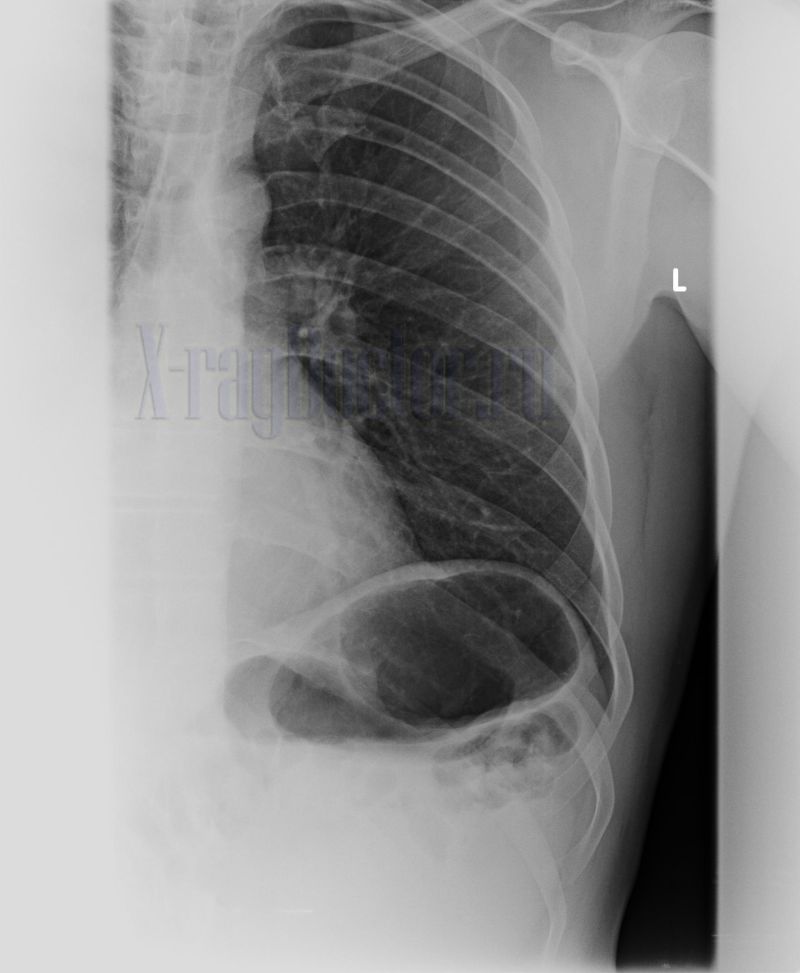

Рентгеновские снимки при врожденной эмфиземе легкого

Раздел: Визуальные уроки